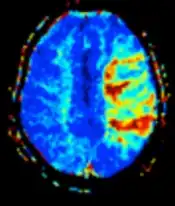

MRI perfusion showing a delayed time-to-maximum flow (Tmax) in the penumbra in a case of occlusion of the left middle cerebral artery.

In cerebral infarction, the penumbra has decreased perfusion.[1] Another MRI sequence, diffusion weighted MRI, estimates the amount of tissue that is already necrotic, and the combination of those sequences can therefore be used to estimate the amount of brain tissue that is salvageable by thrombolysis and/or thrombectomy.[1]